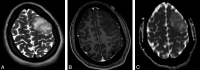

Background and purpose: Oligodendrogliomas are tumors that have variable WHO grades depending on anaplasia and astrocytic components and their treatment may differ accordingly. Our aim was to retrospectively evaluate imaging features of oligodendrogliomas that predict tumor grade.

Materials and methods: The imaging studies of 75 patients with oligodendrogliomas were retrospectively reviewed and compared with the histologic grade. The presence and degree of enhancement and calcification were evaluated subjectively. rCBV and ADC maps were measured. Logistic linear regression models were used to determine the relationship between imaging factors and tumor grade.

Results: Thirty of 75 (40%) tumors enhanced, including 9 of 46 (19.6%) grade II and 21 of 29 (72.4%) grade III tumors (P < .001). Grade III tumors showed lower ADC values compared with grade II tumors (odds ratio of a tumor being grade III rather than grade II = 0.07; 95% CI, 0.02-0.25; P = .001). An optimal ADC cutoff of 925 10(-6) mm(2)/s was established, which yielded a specificity of 89.1%, sensitivity of 62.1%, and accuracy of 78.7%. There was no statistically significant association between tumor grade and the presence of calcification and perfusion values. Multivariable prediction rules were applied for ADC < 925 10(-6) mm(2)/s, the presence of enhancement, and the presence of calcification. If either ADC < 925 10(-6) mm(2)/s or enhancement was present, it yielded 93.1% sensitivity, 73.9% specificity, and 81.3% accuracy. The most accurate (82.2%) predictive rule was seen when either ADC < 925 10(-6) mm(2)/s or enhancement and calcification were present.

Conclusions: Models based on contrast enhancement, calcification, and ADC values can assist in predicting the grade of oligodendrogliomas and help direct biopsy sites, raise suspicion of sampling error, and predict prognosis.